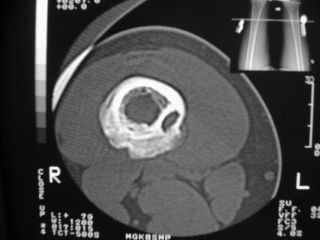

Анамнез практически никакой: в следствие травмы (растяжение связок коленного сустава) от 07.11.2004 выполнены Rg-граммы в травмпункте и обнаружено опухолевидное образование. Первичные Rg-граммы я не публикую, так как они заметно худшего качества, да и динамики за прошедшие три недели не отражают. Болевой синдром купирован в течение трёх дней. В настоящий момент мальчика ничего не беспокоит. Ходьба не нарушена, опухоль пальпируется с трудом по задней поверхности в н\3 правого бедра, пальпация безболезненна, объем движений в суставах правой нижней конечности полный и симметричный. Кожа над опухолью не изменена. В нашей клинике проведено дополнительное обследование: общие анализы крови и мочи, биохимия крови без особенностей. Выполнены Rg-граммы на цифровом Siemens обычные и продольные томограммы срезами 3-5 мм, а также компьютерная томография поперечными срезами по 5 мм. Прошу обратить внимание, что на приведённых томограммах видны две полости 10х15 мм и 15х60 мм. Также имеются два опухолевидных образований наслаивающихся друг на друга: уплощённое и вытянутое 10х100 мм и элипсовидной формы 15х30 мм. Это хорошо заметно на фото a_1.jpg c_1.jpg и d_1.jpg. Плотность внутри полостей 125% от плотности костномозгового канала, плотность наружного опухолевидного образования 55% от плотности кортикального слоя. Также отмечается линия перелома по центру наружного опухолевидного образования. Исходя из полученных данных мнения в плане диагноза несколько разделились от 1)сочетания кортикальной фиброзной дисплазии и латентно протекавшего маршевого перелома н\3 правого бедра до 2)остеосаркомы. В отношении первого варианта не сходится отсутствие клиники при переломе такой крупной кости как бедро, второй вариант вообще оставлю без комментария, ибо некомпетентен. Хотелось бы услышать мнения коллег, с удовольствием ознакомлюсь с любыми предположениями и замечаниями. С уважением, Александр Е. Клоков Отделение детской ортопедии и травматологии БСМП г. Мурманска.